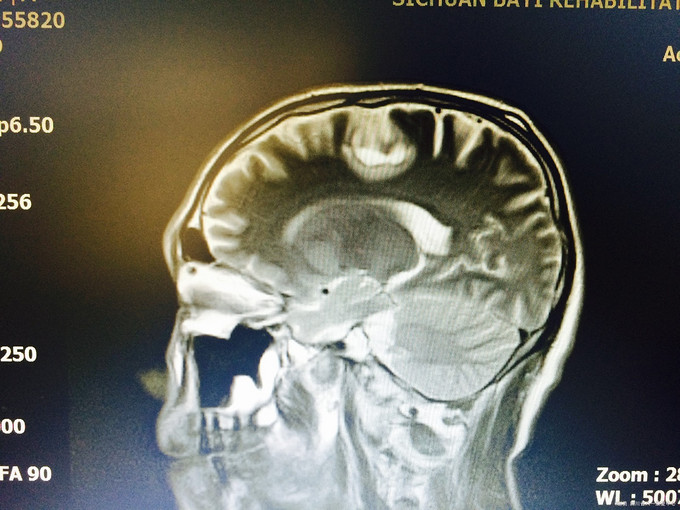

入院查体:生命体征平稳,高级皮层功能正常;四肢肌张力不高,肌力5级,病理征未引出;头颅MRI示:左侧额叶皮层下见23*15*16mm“多囊状”异常信号,见等信号囊壁,周边少许水肿信号,增强信号见病灶壁环形强化,边缘一结节状强化,肿瘤?脑囊虫病?左颞叶、顶叶、颞叶多个结节状,长T1长T2信号,FLAIR呈高信号;左颞叶见一强化“小结节”; 入院诊断:颅内占位改变,性质待定:脑膜瘤?脑囊虫病?